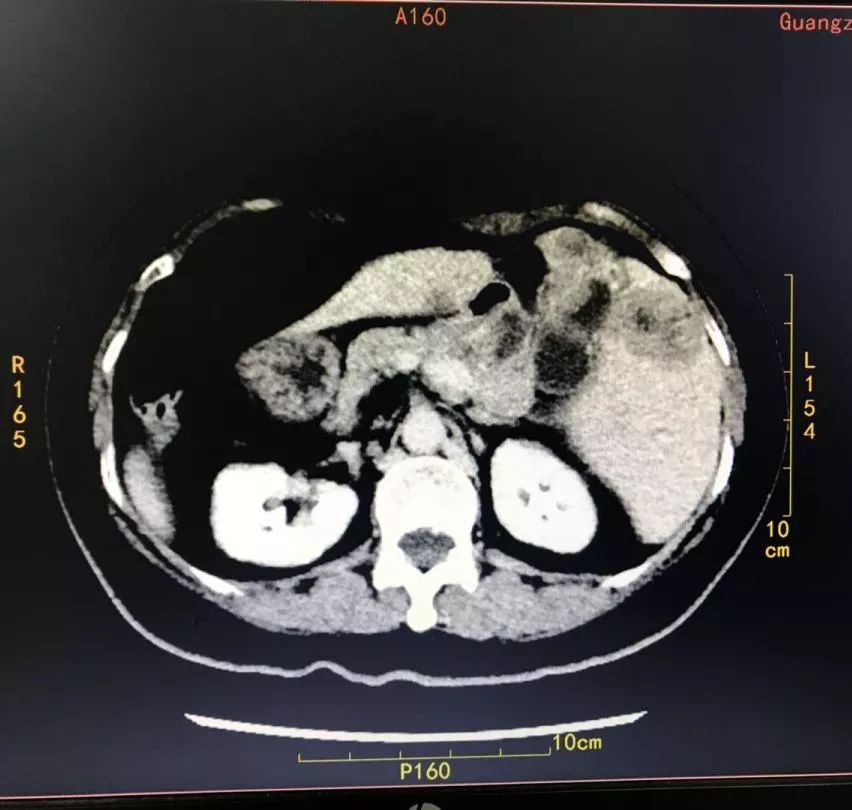

因患者特殊的解剖结构,给内镜下的治疗带来了意想不到的情况。内镜过贲门后见胃粘膜皱襞走行与平时所见相反,沿胃壁走形找到幽门,过幽门口后镜头向下、进境、右旋,到达十二指肠球部,根据肠道走形,向左侧弯曲,内镜向左轻旋、进入十二指肠降段,发现十二指肠乳头,拉直内镜,调整、固定位置和轴向。导丝配合切开刀沿乳头11 点钟方向插管,导丝进入管道,轻点造影剂证实为胰管。考虑全内脏反位,遂将导丝引导切开刀沿乳头1 点钟方向插管,顺利进入胆道,造影显示肝总管至胆总管上段梗阻,长约2cm,肝内外胆管扩张,直径约1.0cm。

CT提示:胆囊癌伴肝内多发转移